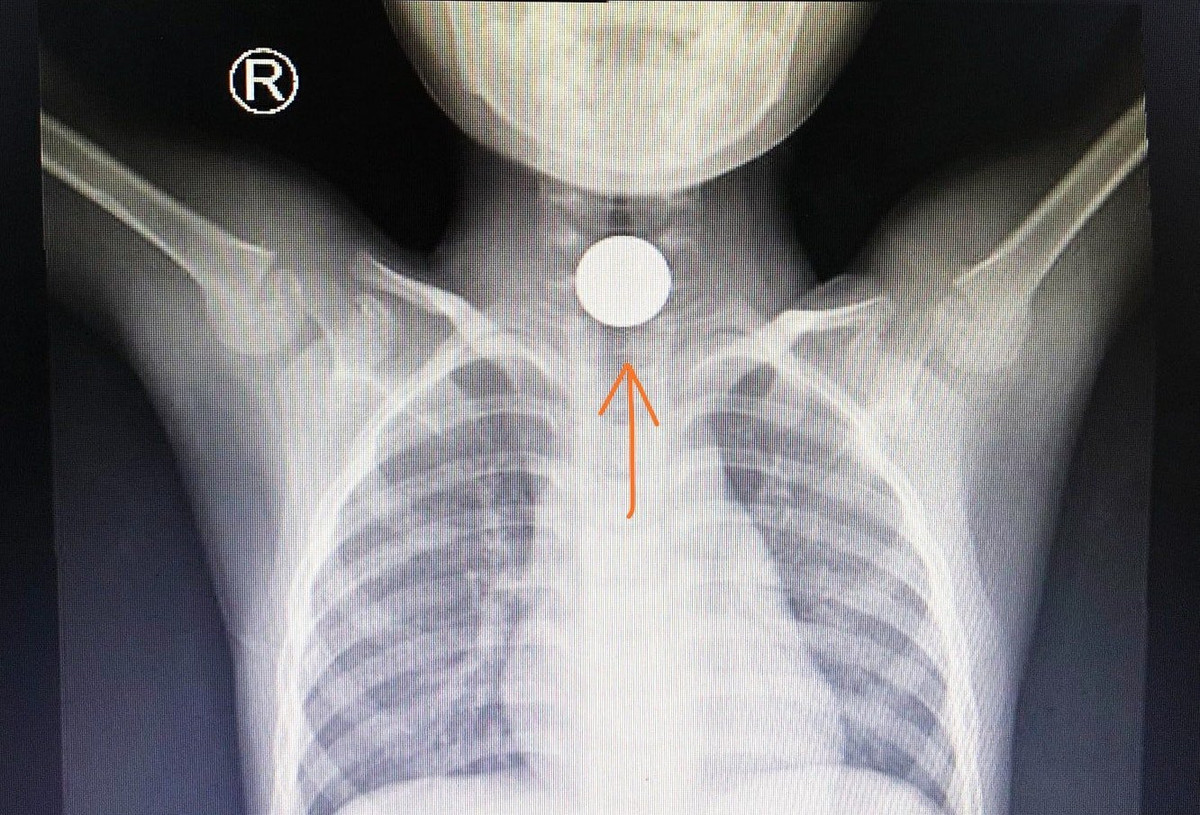

Ngoài tai nạn giao thông, đơn vị này còn tiếp nhận và xử trí nhiều trẻ gặp tai nạn nuốt đồng xu, hóc hạt đậu, dị vật thực quản, phù phổi do ngã xuống ao, uống nhầm xăng, rượu, bỏng nước sôi.

Đồng xu kẹt trong thực quản cho một bệnh nhi 5 tuổi. Ảnh: BVCC.